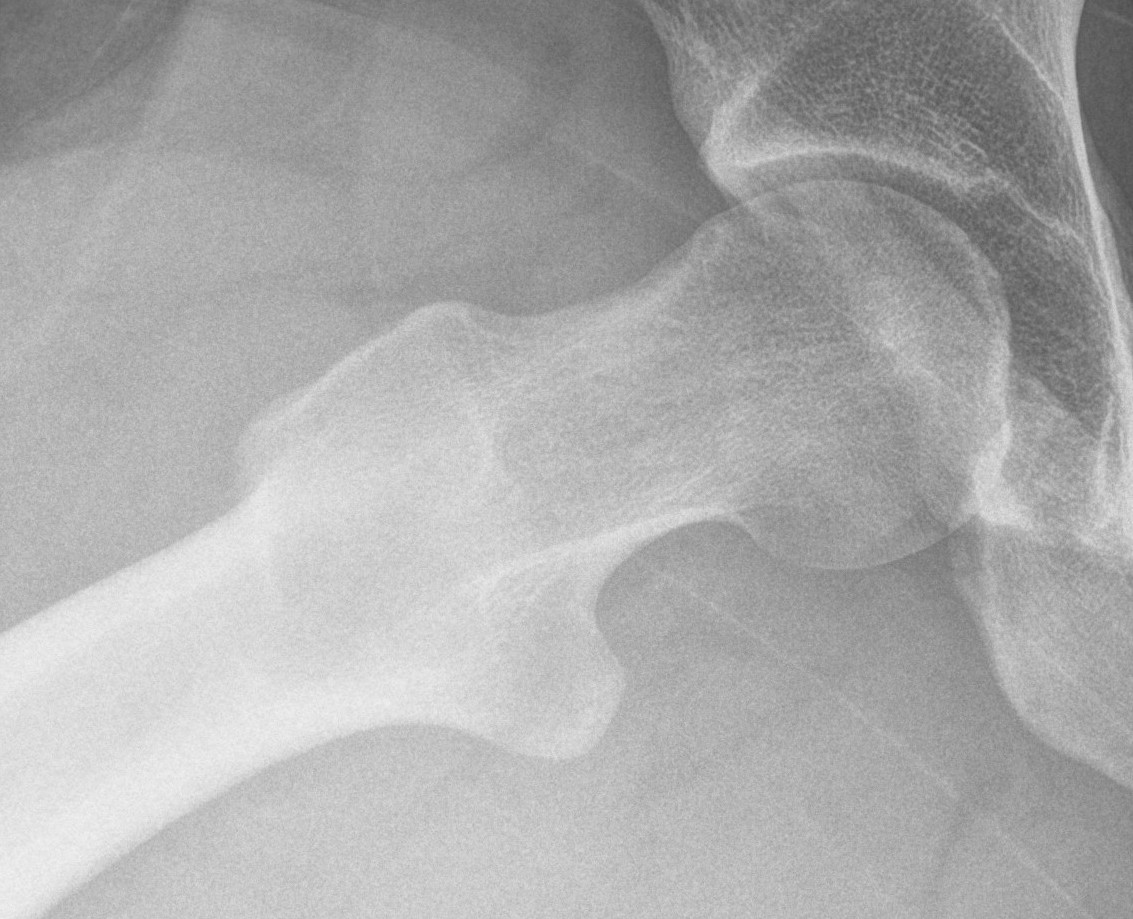

45 and 90 degree Dunn view

Look for Cam morphology

Small Cam on Dunn view Large anterior Cam on Dunn view